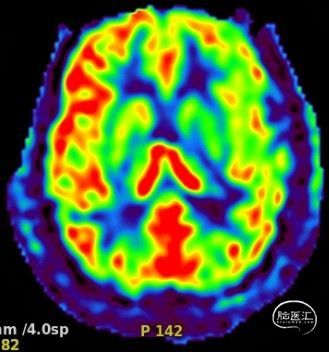

磁共振ASL灌注:左侧大脑半球血流较右侧差: